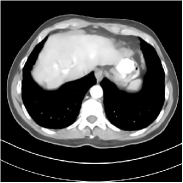

Fig. 2 shows a test example reconstructed using various methods.

Refer to caption

Figure 2: Reconstructions of slice 100 from patient L192 using various methods. The display window is [800 1200] HU.

We observe that PWLS-EP reduces the severe noise and streak artifacts observed in the low-dose FBP images, and the transform learning-based method PWLS-ULTRA further suppresses noise and reconstructs more details of the image such as the zoom-in areas. However, both methods have some blurry artifacts. The standalone FBPConvNet method heavily removes noise and streak artifacts, while introducing several artificial features (e.g., feature indicated by the arrow in the top-right box in Fig. 2). WavResNet denoises the image without introducing artifical features, but still retains some streaks around image boundaries and blurs some details (e.g., feature indicated by the arrow in the bottom-left box in Fig. 2). The state-of-the-art MAP-NN method performs slightly better than WavResNet in terms of suppressing streak artifacts, while it still loses some details as indicated in the zoomed regions. The competing plug-and-play unrolled method—ADMM-Net with WavResNet denoiser—outperforms the standalone WavResNet method, but still has some streak artifacts and blurred details. Compared to these methods, the proposed SUPER methods (SUPER-WRN-EP, SUPER-WRN-ULTRA, SUPER-FCN-EP, and SUPER-FCN-ULTRA) improve the reconstruction quality in terms of removing noise and artifacts, and recovering details more precisely. Two other example comparisons are included in the supplement (Fig. 10 and Fig. 11).